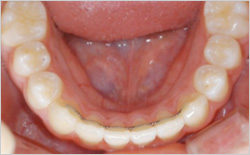

앞니 치아의 안쪽 면에 가느다란 철사를 붙여 치아의 움직임을 예방하는 유지장치입니다.

유지장치를 뺄 수 없기 때문에 칫솔질을 잘 해주셔야 합니다.

고정식 유지장치는 장치 주변으로 치석이 생길 수 있기 때문에 올바른 방법으로 잘 닦아 주어야 합니다.

만약 철사가 치아에서 탈락되면 치아가 움직일 수도 있으므로 빨리 치과에 오셔서 다시 부착해야 합니다.